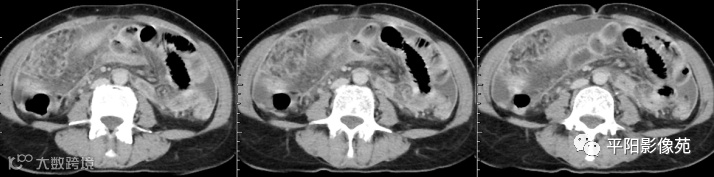

腹部增强 延迟期